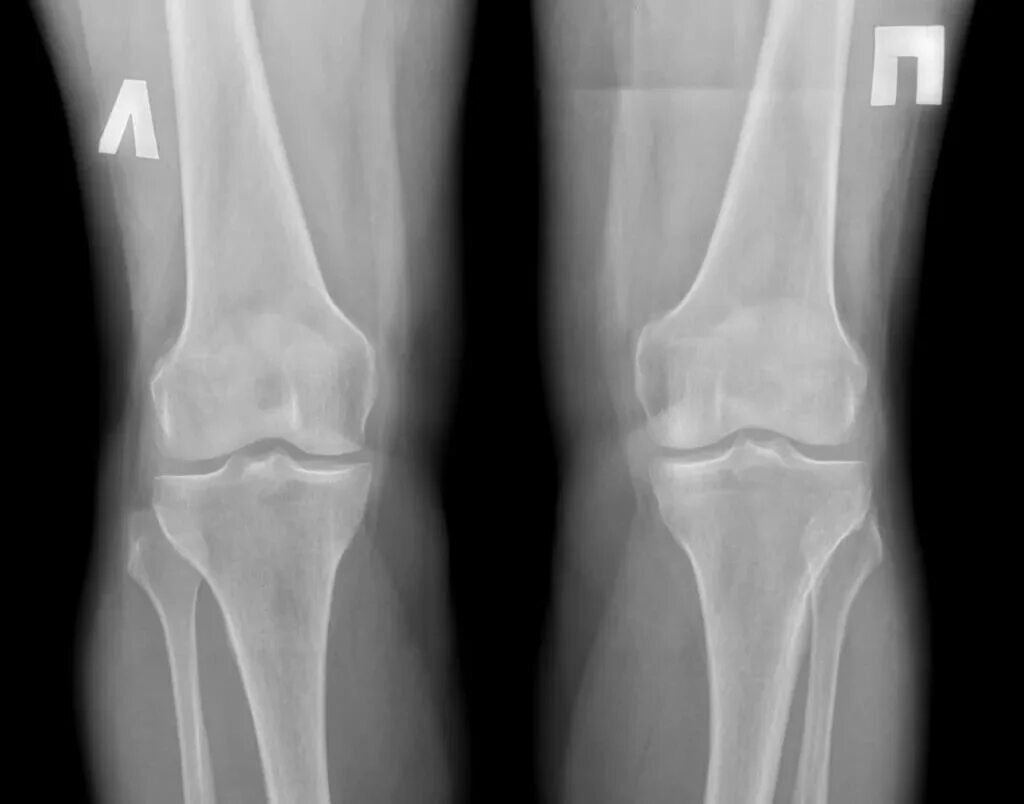

Дисторсия коленного